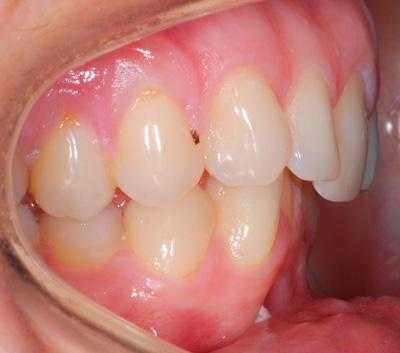

Внутриротовые признаки

В полости рта дистальный прикус определяется по выступающим вперед верхним фронтальным зубам. В норме, при ортогнатическом прикусе, верхние резцы перекрывают нижние примерно на 1/3. При дистальной патологии между верхними и нижними резцами образуется расстояние — «саггитальная щель».

- I подкласс — верхние резцы направлены вперед, иногда немного вверх. Для этого вида дистальной окклюзии характерная саггитальная щель.

- II подкласс — передние зубы растут по направлению назад, смыкаются с нижними резцами, саггитальная щель отсутствует.